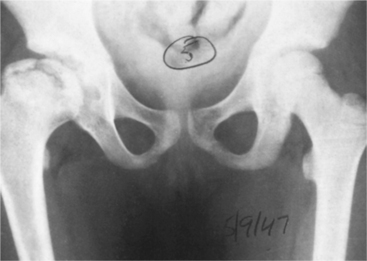

Figure 27-27 Radiograph of lower pelvis in Legg-Calvé-Perthes disease after revascularization of the necrotic femoral head shows enlargement of the head, with the original necrotic ossification center seen as a “head within a head.” (From Bullough PG: Orthopaedic pathology, ed 3, London, 1997, Mosby-Wolfe, p 263.)

The disease process consists of four stages lasting from 2 to 5 years (Table 27-3 and Fig. 27-27). Because the growth plate of the femoral head lies above the insertion of the capsule of the hip joint in children and because the epiphyseal plate acts as a firm barrier to blood flow between the metaphysis and epiphysis, the femoral head depends on vessels that track along the surface of the neck of the femur to enter the epiphysis above the growth plate.